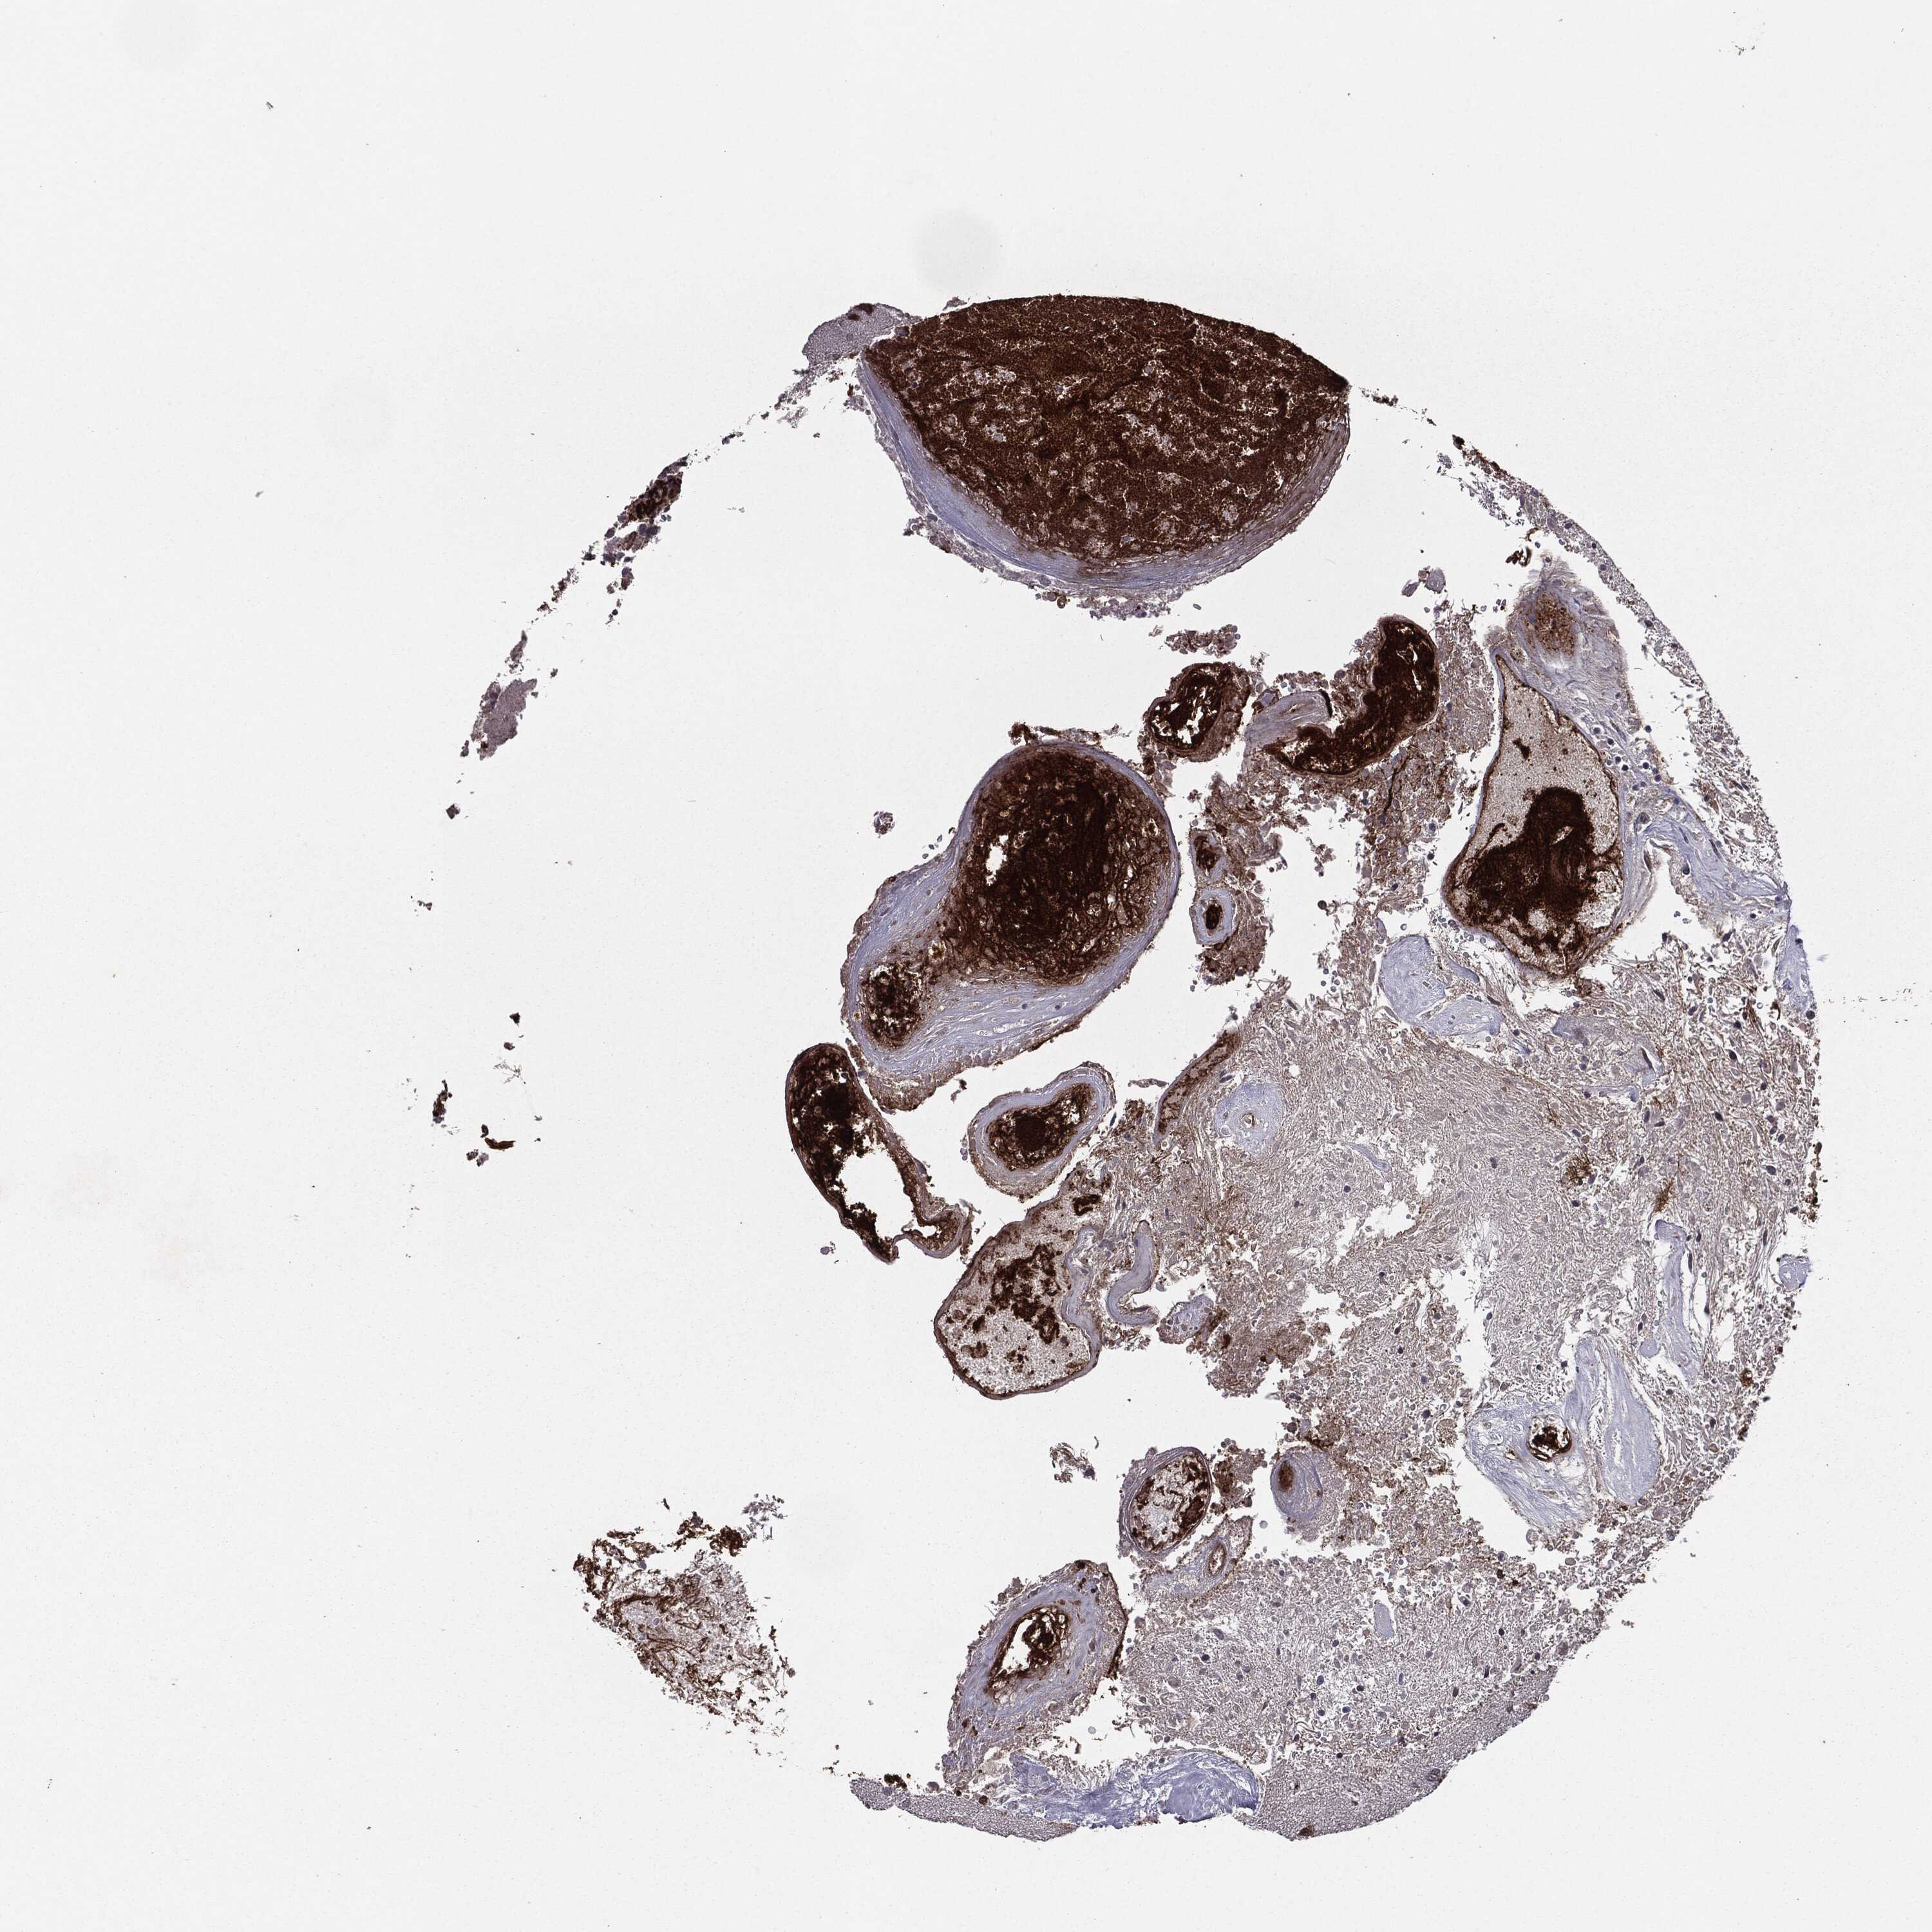

GLIOMA - Protein expressioni

A mouse-over function shows sample information and annotation data. Click on an image to view it in a full screen mode. Samples can be filtered based on level of antibody staining by selecting one or several of the following categories: high, medium, low and not detected. The assay and annotation is described here.

Note that samples used for immunohistochemistry by the Human Protein Atlas do not correspond to samples in the TCGA dataset.

Antibody stainingi

Antibody staining in the annotated cell types in the current human tissue is reported as not detected, low, medium, or high, based on conventional immunohistochemistry profiling in selected tissues. This score is based on the combination of the staining intensity and fraction of stained cells.

Each image is clickable and will lead to virtual microscopy that enables deeper exploration of all samples and also displays staining intensity scores, fraction scores and subcellular localization as well as patient and tissue information for each sample.

Antibody HPA052606

Antibody HPA077139

Staining

High

Medium

Low

Not detected

Intensity

Strong

Moderate

Weak

Negative

Quantity

>75%

75%-25%

<25%

None

Location

Nuclear

Cytoplasmic/membranous

Cytoplasmic/membranous,nuclear

Glioma, malignant, Low grade

Glioma, malignant, High grade

Glioma, malignant, NOS